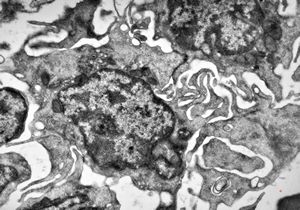

M,58y. | spleen - thesaurismosis of unknown origin … postmedicamentous?

M,44y. | spleen - Gaucher disease